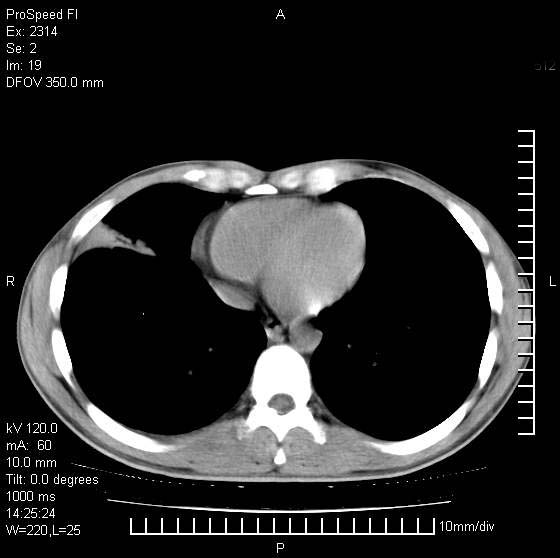

男性,再生障碍性贫血,入院前发热10天,最高40c,右侧胸痛,外院ct示右上,中肺边缘模糊的球性影(就是我现在图中标示的范围),考虑炎症,在我院使用头孢呋辛,洛美沙星10天,高烧消退,自感下午稍有发热,但今天ct示右上,中肺病灶明显扩大,还是考虑炎症,看其中的球型影是否霉菌感染??,是否能排除结核?

右肺中叶外侧段病变,上缘界限不清,下缘锐利,以段性发病为主,内见巨大空洞及空洞内容物,结合病史首先考虑:化脓性肺炎。不除外霉菌感染!

考虑霉菌感染.理由1\\有临床基础疾病,2\\有坏死的空腔,其内可见软组织影.

片状高密度影内见空洞影,内可见球形软组织密度影,并有新月征,考虑霉菌感染.